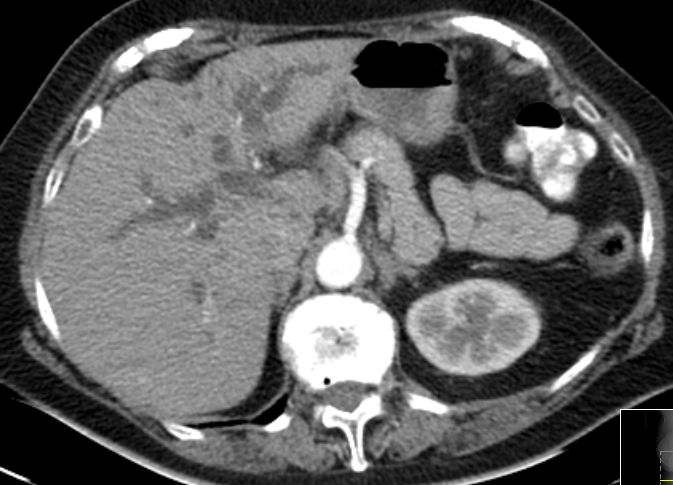

| Pankreasschwanz | 55-jähriger Mann mit Pankreasschwanz-Karzinom, Lebermetastasen, Ascites![]() | |